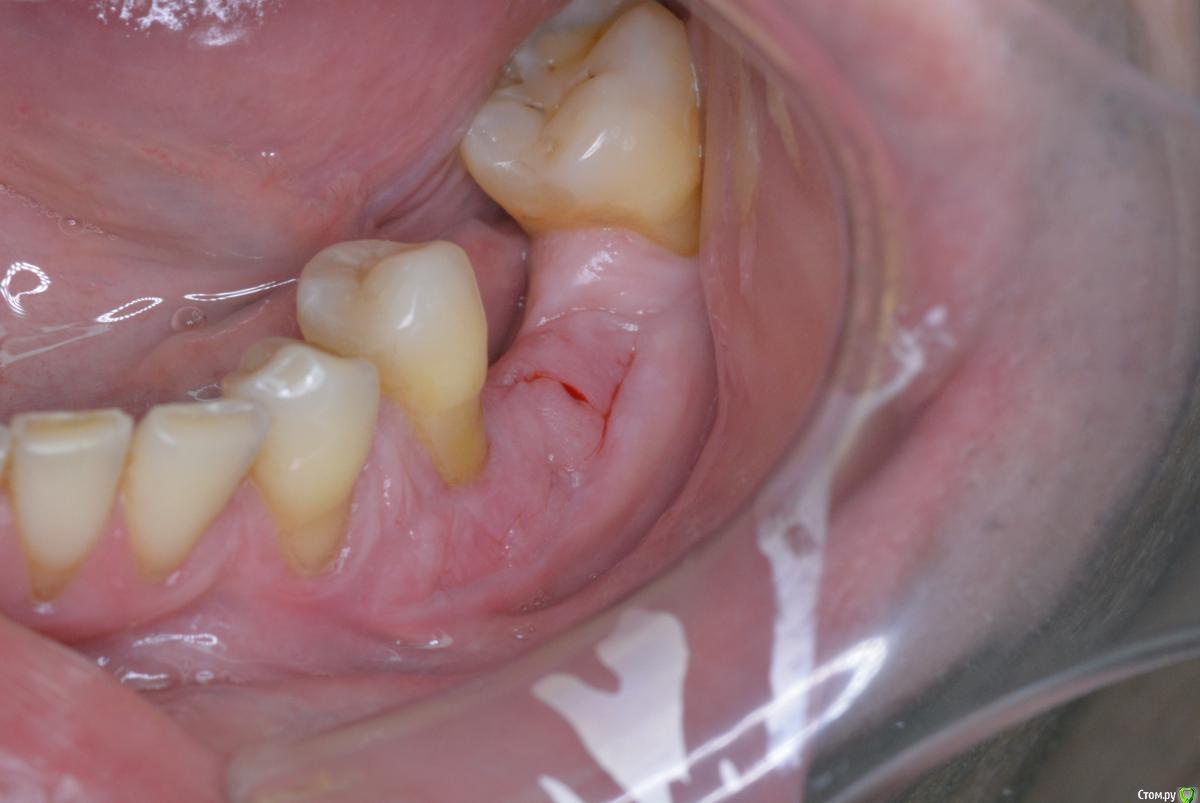

Paco Rabanne Опубликовано 27 октября, 2015 Поделиться Опубликовано 27 октября, 2015 Помогите пожалуйста в планировании.Пациент крупный мужчина, спортсмен, ест много.Зона 36зуба. Медио-дист расстояние по кости около 14мм, в полости рта 11мм. Медиальный наклон 37з. Ортодонтия исключена. Тонкий биотип тканей. Предварительно проведено увеличение зоны прикрепленной десны.Вопросы:1.Сколько ставите имплантов в подобной ситуации? Для одного импланта много места, для двух будет мешать 37 (его фрезой будешь задевать наверное).2. Как лучше аугментировать? Одномоментно с имплантацией, или лучше сначало аугментация (ваш вариант метода) , а потом имплантация?Фото на момент снятия швов после СДТ. Спасибо всем кто отзовется. Понимаю, что сколько людей столько и мнений, интересстны все. Ссылка на комментарий